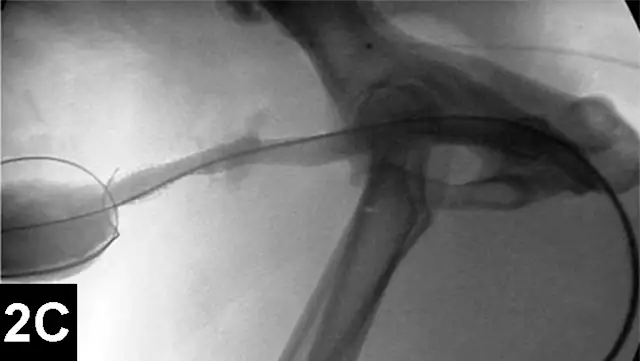

IR techniques that involve placement of an intraluminal stent to alleviate signs associated with malignant obstructions have been described in veterinary patients (Figure 2).5 The author has performed multiple palliative stenting procedures in the urinary tract and upper and lower GI tracts and has relieved luminal obstructions caused by neoplasia or intractable benign strictures in many different sizes of animals, including ferrets.5-11 The IR techniques were fast, safe, and effective. Complications were minor and uncommon.

Figure 2A: Serial lateral positive contrast urethrocystograms in a dog with a malignant urethral obstruction secondary to a prostatic tumor.

Maximal urethral diameters measured using a colonic marker catheter to adjust for radiographic magnification.